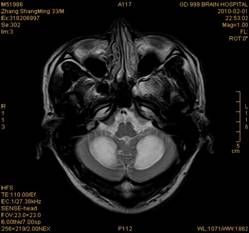

案例1 患者,男,33岁, 海洛因脑病的头颅MR。表现为双侧大脑后部皮层下白质、双侧内囊后肢、枕叶白质、胼胝体压部、中脑、桥脑、双侧小脑半球齿状核质及双侧桥臂多发对称性片状及斑片状长T1长T2异常信号影,FLAIR序列呈高信号,其中双侧内囊后肢表现为特异的“八字征”,双侧小脑半球齿状

核质表现为对称的“蝶翼征”,脑干病变呈“蟹钳征”及“中空征”。增强后双侧半卵圆中心、双侧枕叶白质及双侧小脑半球病变内或边缘中度强化影。给予患者抗炎、脱水、疏通血管及营养神经等药物治疗,一个月后痊愈出院。